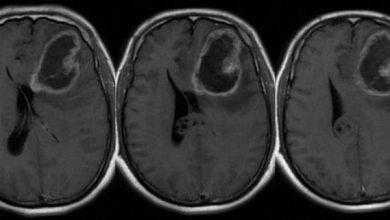

دراسة تشير إلى إمكانية استخدام فيروس زيكا لعلاج سرطانات الدماغ القاتلة

في الآونة الأخيرة تفشت حالات فيروس زيكا مسببة عيوبا في أدمغة الأطفال وهم أجنة، إلا أنه وعلى عكس المتوقع، في…